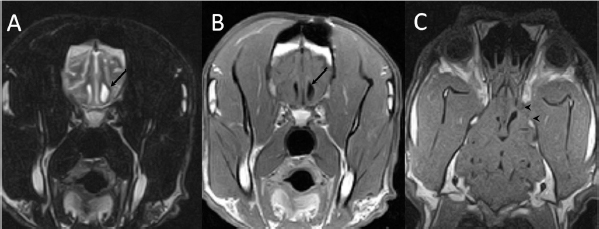

A 3-year-old female Great Dane was referred for acute onset behavioral changes (aggression and disorientation) of 2 weeks duration, and seizures from 24 hours prior to presentation. Physical examination revealed no abnormalities in body temperature, body condition score, heart rate, pulse quality, or cardiopulmonary auscultation. All lymph nodes were considered of normal size and no pain was elicited upon manipulation of the orbital, aural, or cranial musculature. Neither was there any history of dermatological or traumatic lesions in the eye, ear, or mouth. The neurological examination revealed the patient to be obtunded with decreased postural reactions and menace response worse in the left side. Neuroanatomic lesion localization was considered focal in the right prosencephalon with a possible increase in intracranial pressure. Hematological and serum biochemical analysis showed no abnormalities. Magnetic resonance imaging was performed using a low-field magnet (Airis Mate; Hitachi, Tokio, Japan). The study revealed a left-sided single frontal intra-axial lesion affecting gray and white matter adjacent to the internal capsule at the level of the optic canal (Fig. 1). The lesion presented signal homogeneity characterized by hyperintensity on T2W and FLAIR sequences and hypointensity in T1W sequences with peripheral enhancement after intravenous contrast administration (Fig. 1A and 1B). The lesion had a round shape with the greatest diameter of 2.84 cm. This enhancement was also recognized in the surrounding meninges following the brain surface following sulci. A small linear tract observed was directed dorsally from the lesion through the corona radiata (Fig. 1B). The lesion was associated with extensive perilesional vasogenic edema that worsened the mass effect characterized by a midline shift. The orbital and medial pterygoid muscles also showed an intense enhancement (Fig. 2). The wing of the presphenoid bone was thinner than the contralateral bone (Fig. 1B). A CT scan (Astelion 16, Toshiba, Tokio, Japan) was performed after MRI that allowed the identification of osteolysis in the presphenoid bone immediately dorsal to the orbital fissure (Fig. 1C). CT scan also revealed a hypoattenuating intra-axial lesion located in the left frontoparietal lobe together with diffuse hypoattenuation of tissues adjacent to the left optic nerve and the left pterygoid muscle. Finally, CSF analysis showed no abnormalities. On the basis of advanced radiological findings, the main differential diagnosis was an intracranial abscess due to the extension of the extracranial septic process through presphenoid bone. Because of rapid neurologic deterioration and suspected increased intracranial pressure, surgical excision was planned. A modified left rostrotentorial craniectomy was performed. Temporalis muscle and fascia were retracted, extending the incision cranially through the temporal line. Once the frontal and presphenoid bones were exposed an area of osteolysis was observed in the wing of the presphenoid bone immediately dorsal to the orbital fissure. The craniectomy (approximately 3 cm diameter) was centered on the osseous defect. A mucopurulent discharge presented immediately after the incision of the dura mater. A sample was collected for its microbiological study. The surgical site was flushed with sterile saline revealing the tip of a grass awn which was extracted from the brain parenchyma together with a small amount of purulent fluid (Fig. 3). After extensive flushing, the meninges were left open to allow drainage and the incision was closed as per routinely. Postoperative CT showed the correct location of the craniectomy and resolution of the abscess which was substituted by gaseous content but remained inside and on the dorsal surface of the frontal lobe (Fig. 4). Immediate postoperative therapy consisted of amoxicillin + clavulanic acid (Synulox 500, Zoetis Spain SL) 22 mg/kg PO, q8h; marbofloxacin (Marbocyl P80, Vetoquinol SA) 5 mg/kg PO, q24h; metronidazole (Flagyl 250, Sanofi-aventis SA) 15 mg/kg PO, q12h; prednisone (Prednisona Kern Pharma 30mg, Kern Pharma) 0.5 mg/kg PO, q12h; tramadol (Tramadol retard Combix 100 mg, Laboratorios Combix S.L.U) 2 mg/kg PO, q8h; famotidine (Famotidina Normon 40 mg; Laboratorios Normon SA) 0.7 mg/kg PO, q24h; and phenobarbital (Phenoleptil 100 mg, Le Vet BV) 2.5 mg/kg PO, q12h. Cultured samples were positive for Pseudomonas aeruginosa sensitive to ciprofloxacin, imipenem, and amikacin among other antibiotics. Based on these results, antibiotic therapy was changed to ciprofloxacin (Ciprofloxacino 500, Laboratorios Normon SA) 10 mg/kg PO, q12h and metronidazole 15 mg/kg PO, q12h for 2 months. Prednisone, tramadol, and famotidine were withdrawn and phenobarbital was maintained at 2.5 mg/kg q12h. Six-month post-operative revision magnetic resonance revealed no signs suggesting the existence of an inflammatory process (Fig. 5). In the area where the abscess had been located, a fluid-filled cavity suggesting being CSF was observed. One year follow-up revealed the patient had seizures every 3 months with neurological examination remaining normal. The patient died 2 years later of unrelated causes.

Fig. 1. (A) Transverse T2-weighted image, (B) transverse post-contrast T1-weighted image, and (C) transverse CT image obtained at the level of the optic canal (asterisk). The lesion can be seen as a hyperintense (arrow in A) and ring-enhancing mass (arrow in B) located in the left frontal lobe. Note thinning of the wing of the presphenoid bone (arrowheads in B and C).